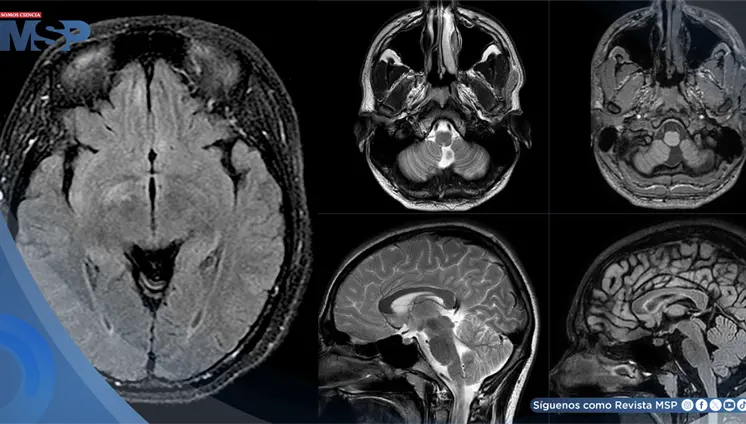

La enfermedad avanzó de forma silenciosa durante años, manifestándose únicamente con cambios de personalidad, deterioro cognitivo e incontinencia, lo que llevó a un diagnóstico tardío.

Aunque inicialmente se sospechó un síndrome de Dandy-Walker, los estudios de neuroimagen revelaron el signo del diente molar y un vermis cerebeloso displásico, hallazgos característicos del síndrome de Joubert.